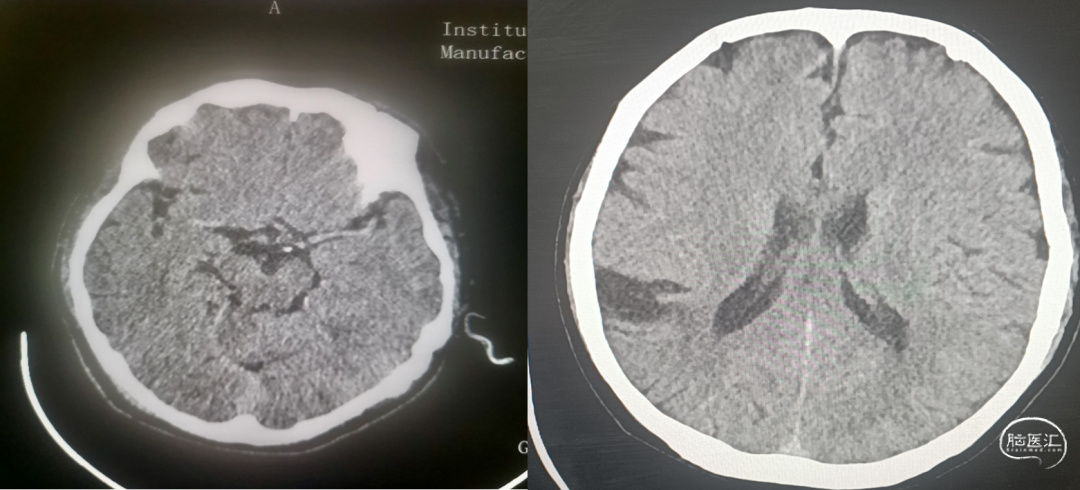

头颅CT未见明显出血及占位,Aspect评分:9分。

24小时后复查头颅CT未见出血,左侧颞枕叶新发低密度灶,考虑脑梗死。

4. 术后12天复查头颅CT未见出血,停用氯吡格雷,给予利伐沙班 15mg 抗凝。